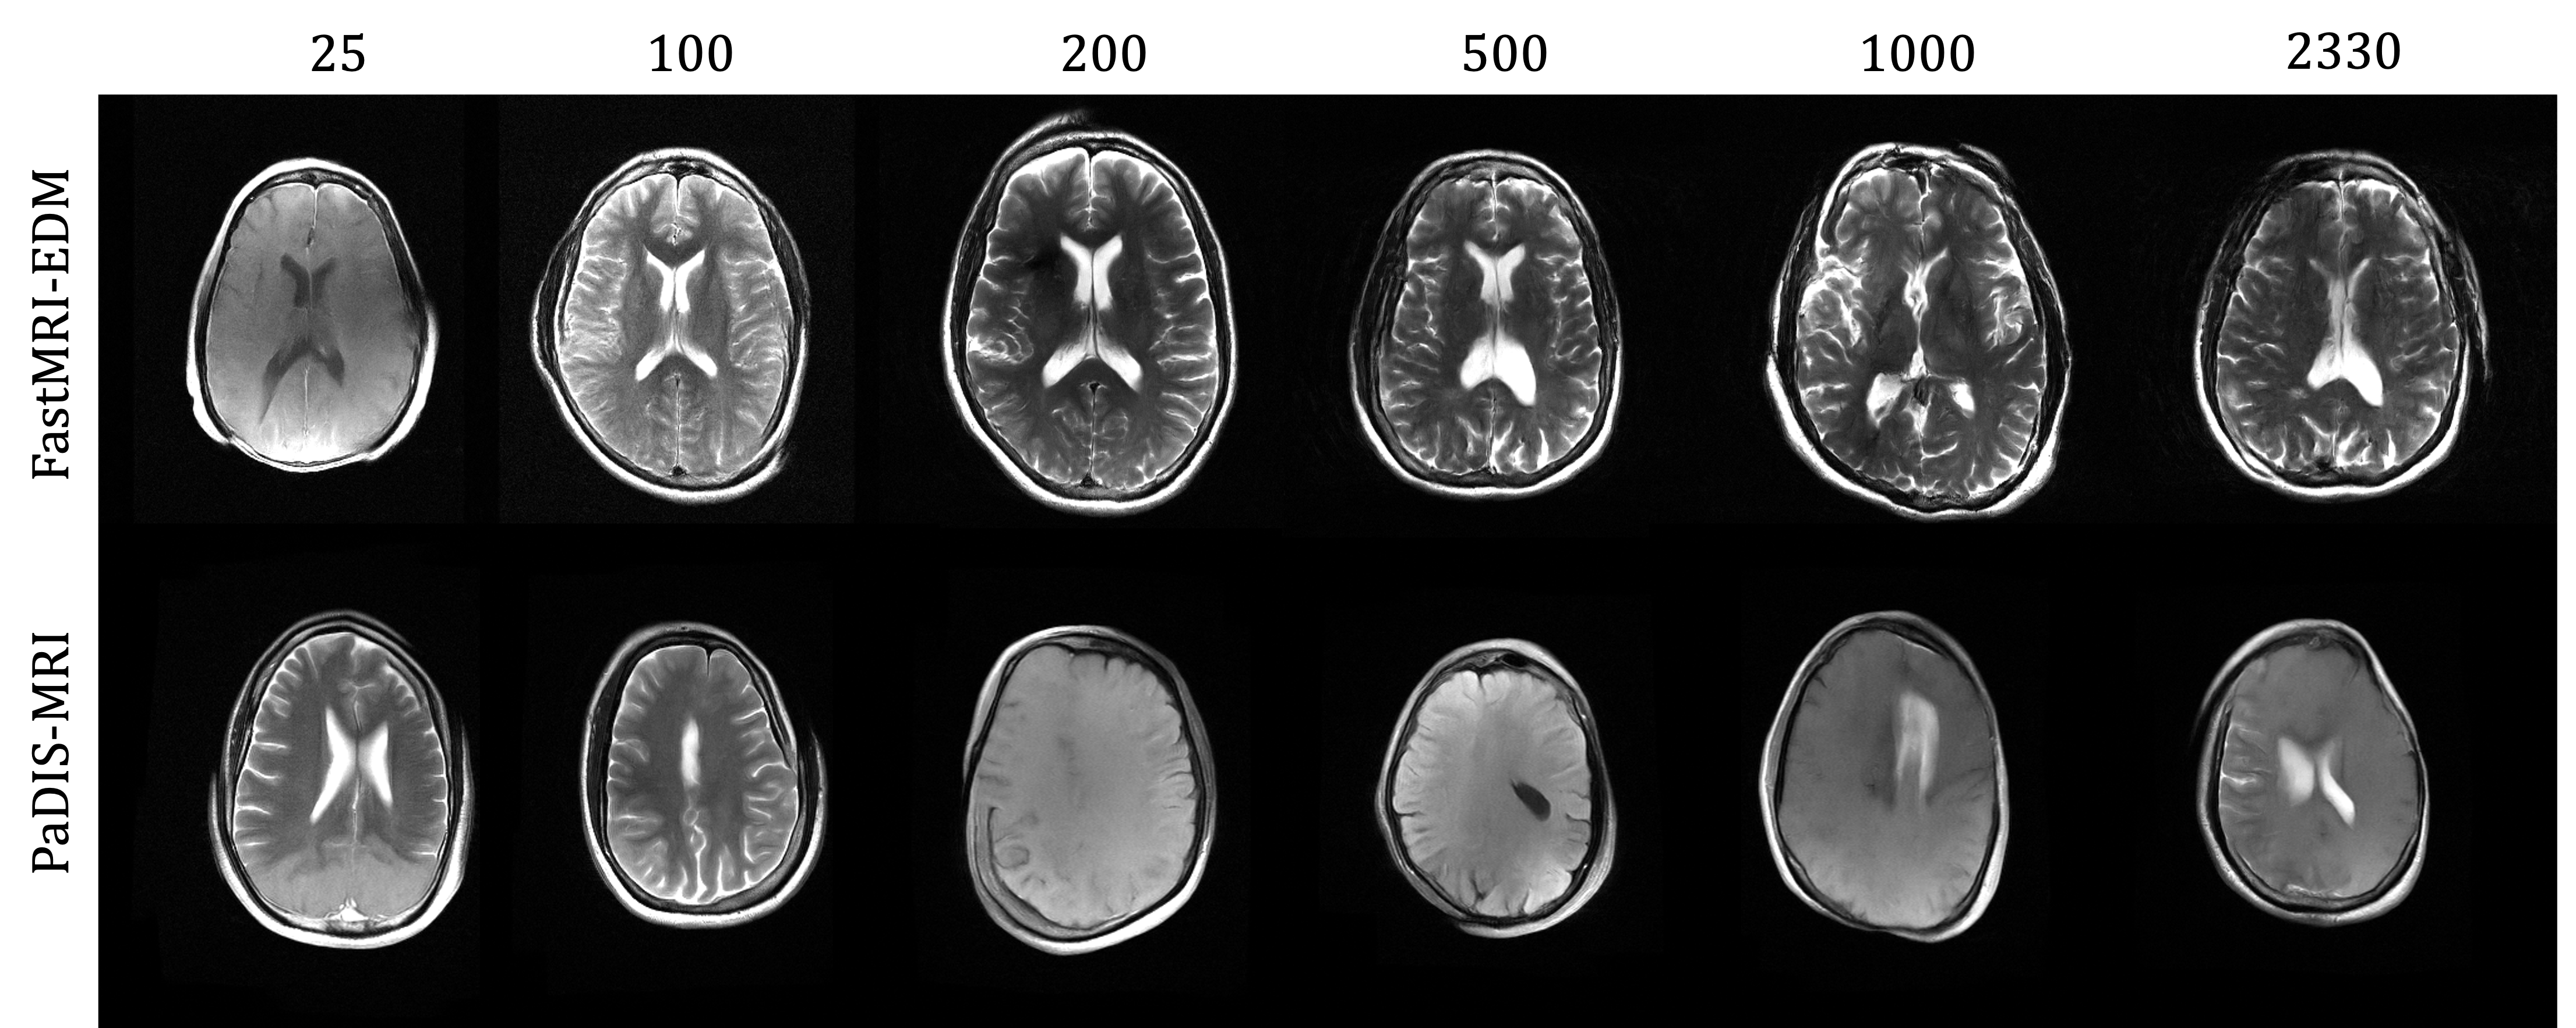

We evaluate the performance of PaDIS-MRI, FastMRI-EDM, and MoDL when trained on dataset sizes S={25,100,200,500,1000,2330}S=\{25,100,200,500,1000,2330\} k-space slices and tested on our evaluation dataset with a fixed acceleration (undersampling) factor of R=7R=7. Figure 1 and Table 5 in Appendix C.1 summarize our findings. Across training set sizes 25 through 500, PaDIS-MRI consistently outperforms the baselines on all metrics. At larger dataset sizes (S1000S\geq 1000), PaDIS-MRI maintains superior PSNR and NRMSE, while FastMRI-EDM shows marginal improvement in SSIM. This small SSIM advantage is likely caused by the whole-image model’s ability to capture global perceptual features when provided sufficient training examples, while PaDIS-MRI’s patch-based approach continues to excel at preserving fine details and minimizing overall error (as reflected in better PSNR and NRMSE). PaDIS-MRI exhibits the most significant advantages as dataset size decreases, highlighting the improved data efficiency of the patch-based approach. Importantly, FastMRI-EDM (and PaDIS-MRI) outperforms MoDL, supporting the results in aali2024robustmulticoilmrireconstruction. Full tabular results including performance stratified by contrast type are presented in Appendix C.1.

Figure 2 provides a visual comparison of the reconstruction quality of each method on example slices. In reconstructions from the S=25,R=7S=25,R=7 models, FastMRI-EDM exhibits slightly more blurring and loss of fine structural details, particularly in regions with complex anatomical features. PaDIS-MRI, in contrast, preserves sharper boundaries and finer details. This enhanced data efficiency can be attributed to the patch-based prior’s ability to learn localized structural motifs more effectively from limited examples. Figure 6 in the Appendix shows similar reconstructions at S=200,R=7S=200,R=7 where FastMRI-EDM more closely approaches the performance of PaDIS-MRI but still struggles with highly detailed anatomy. At both dataset sizes, MoDL underperforms the diffusion priors. In Figure 2, MoDL’s FLAIR reconstruction exhibits pronounced artifacts, likely reflecting reduced generalizability of a supervised prior when the training distribution underrepresents FLAIR.